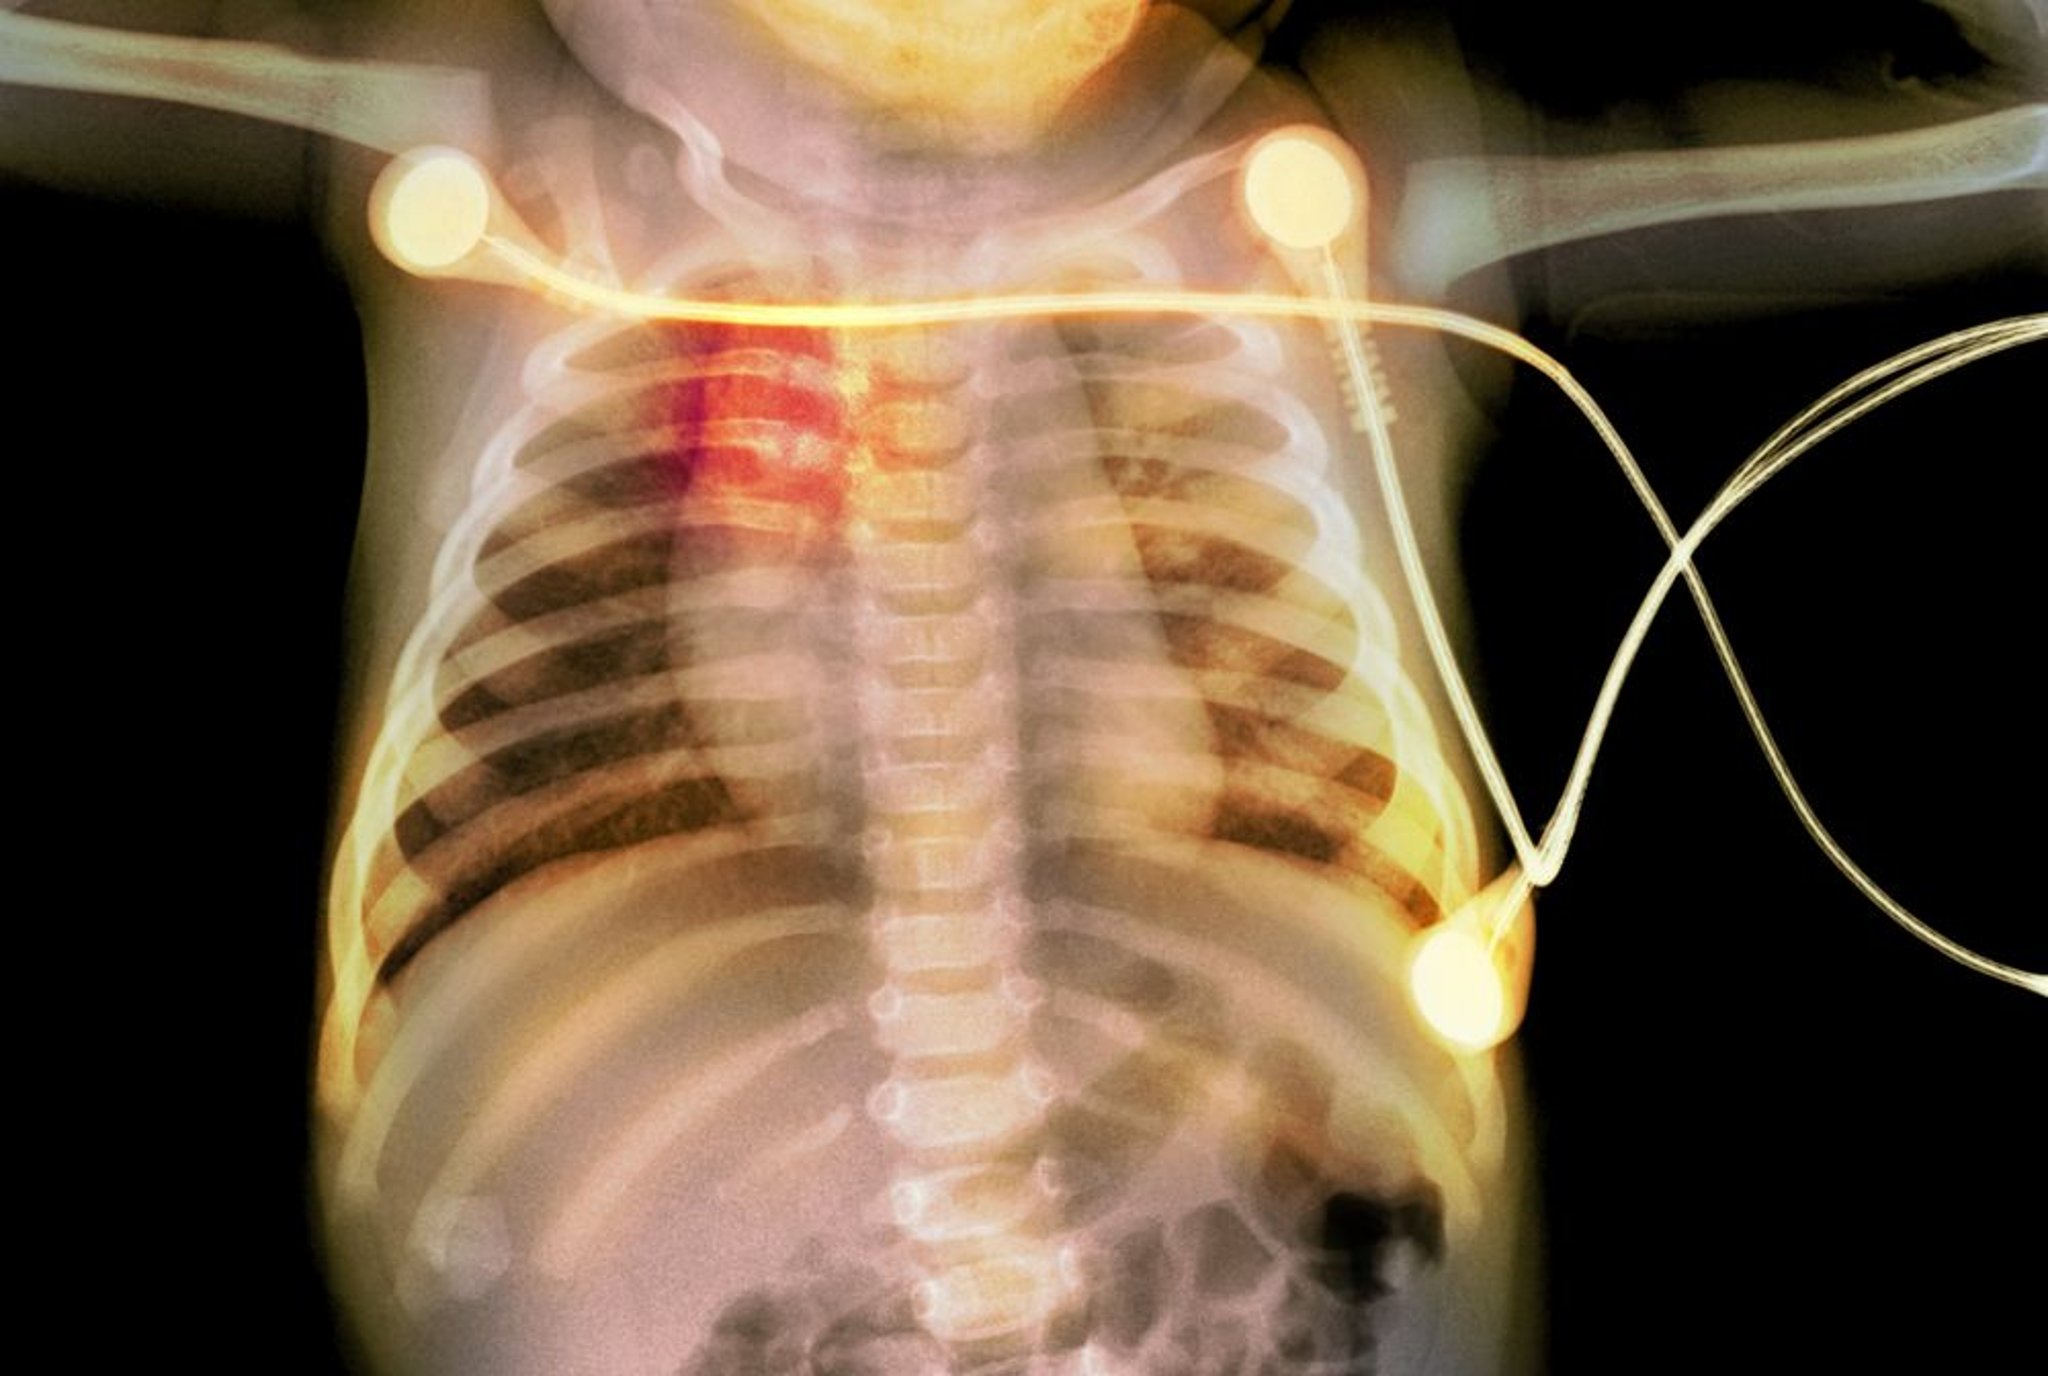

Fractures de côtes chez un bébé

Cette radiographie montre des fractures de côtes (mises en évidence en rouge) chez un bébé, évoquant un cas de maltraitance infantile.

PHOTOSTOCK-ISRAEL/SCIENCE PHOTO LIBRARY